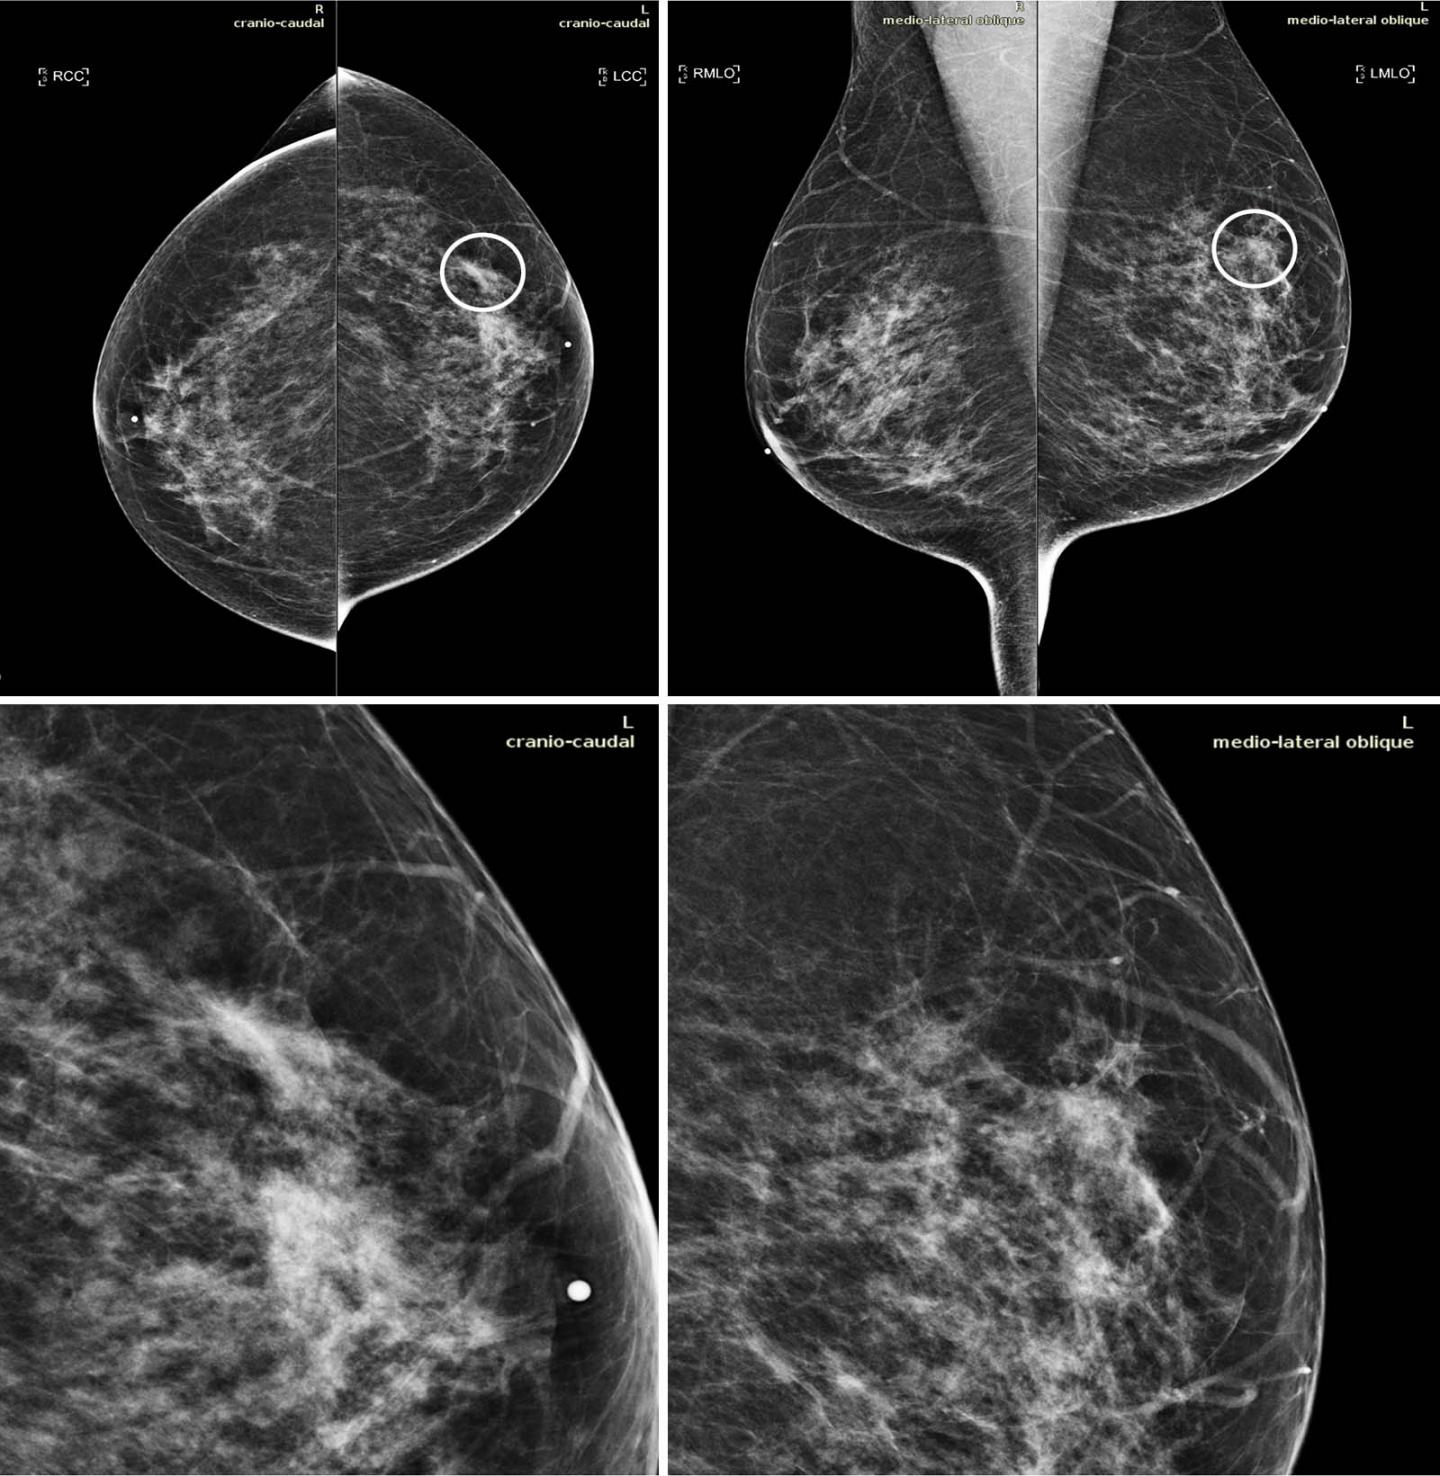

image: Mammograms in a 51-year-old woman with invasive ductal carcinoma. The upper panels show the craniocaudal and the mediolateral oblique views. The lower panels show a close-up of the left breast area containing the lesion. The case is one of the false-negative cases included in the dataset. Accordingly, the initial screening assessment was a BI-RADS 2, meaning visible findings were judged as benign. After 1 year, the patient presented for another screening examination. This time, a focal asymmetry with associated distortion within the left breast was noticed; the patient was recalled and diagnosed with a 1.5-cm mass in the upper outer quadrant of the left breast on the craniocaudal view (circle).

Image: